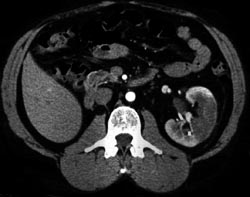

Diagnosis

Iliac Grafts